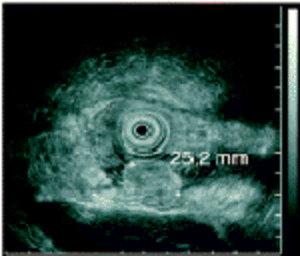

Kl. Pathologie und Genetik neuroendokriner Tumore | Fallberichte | Klinische Studien |